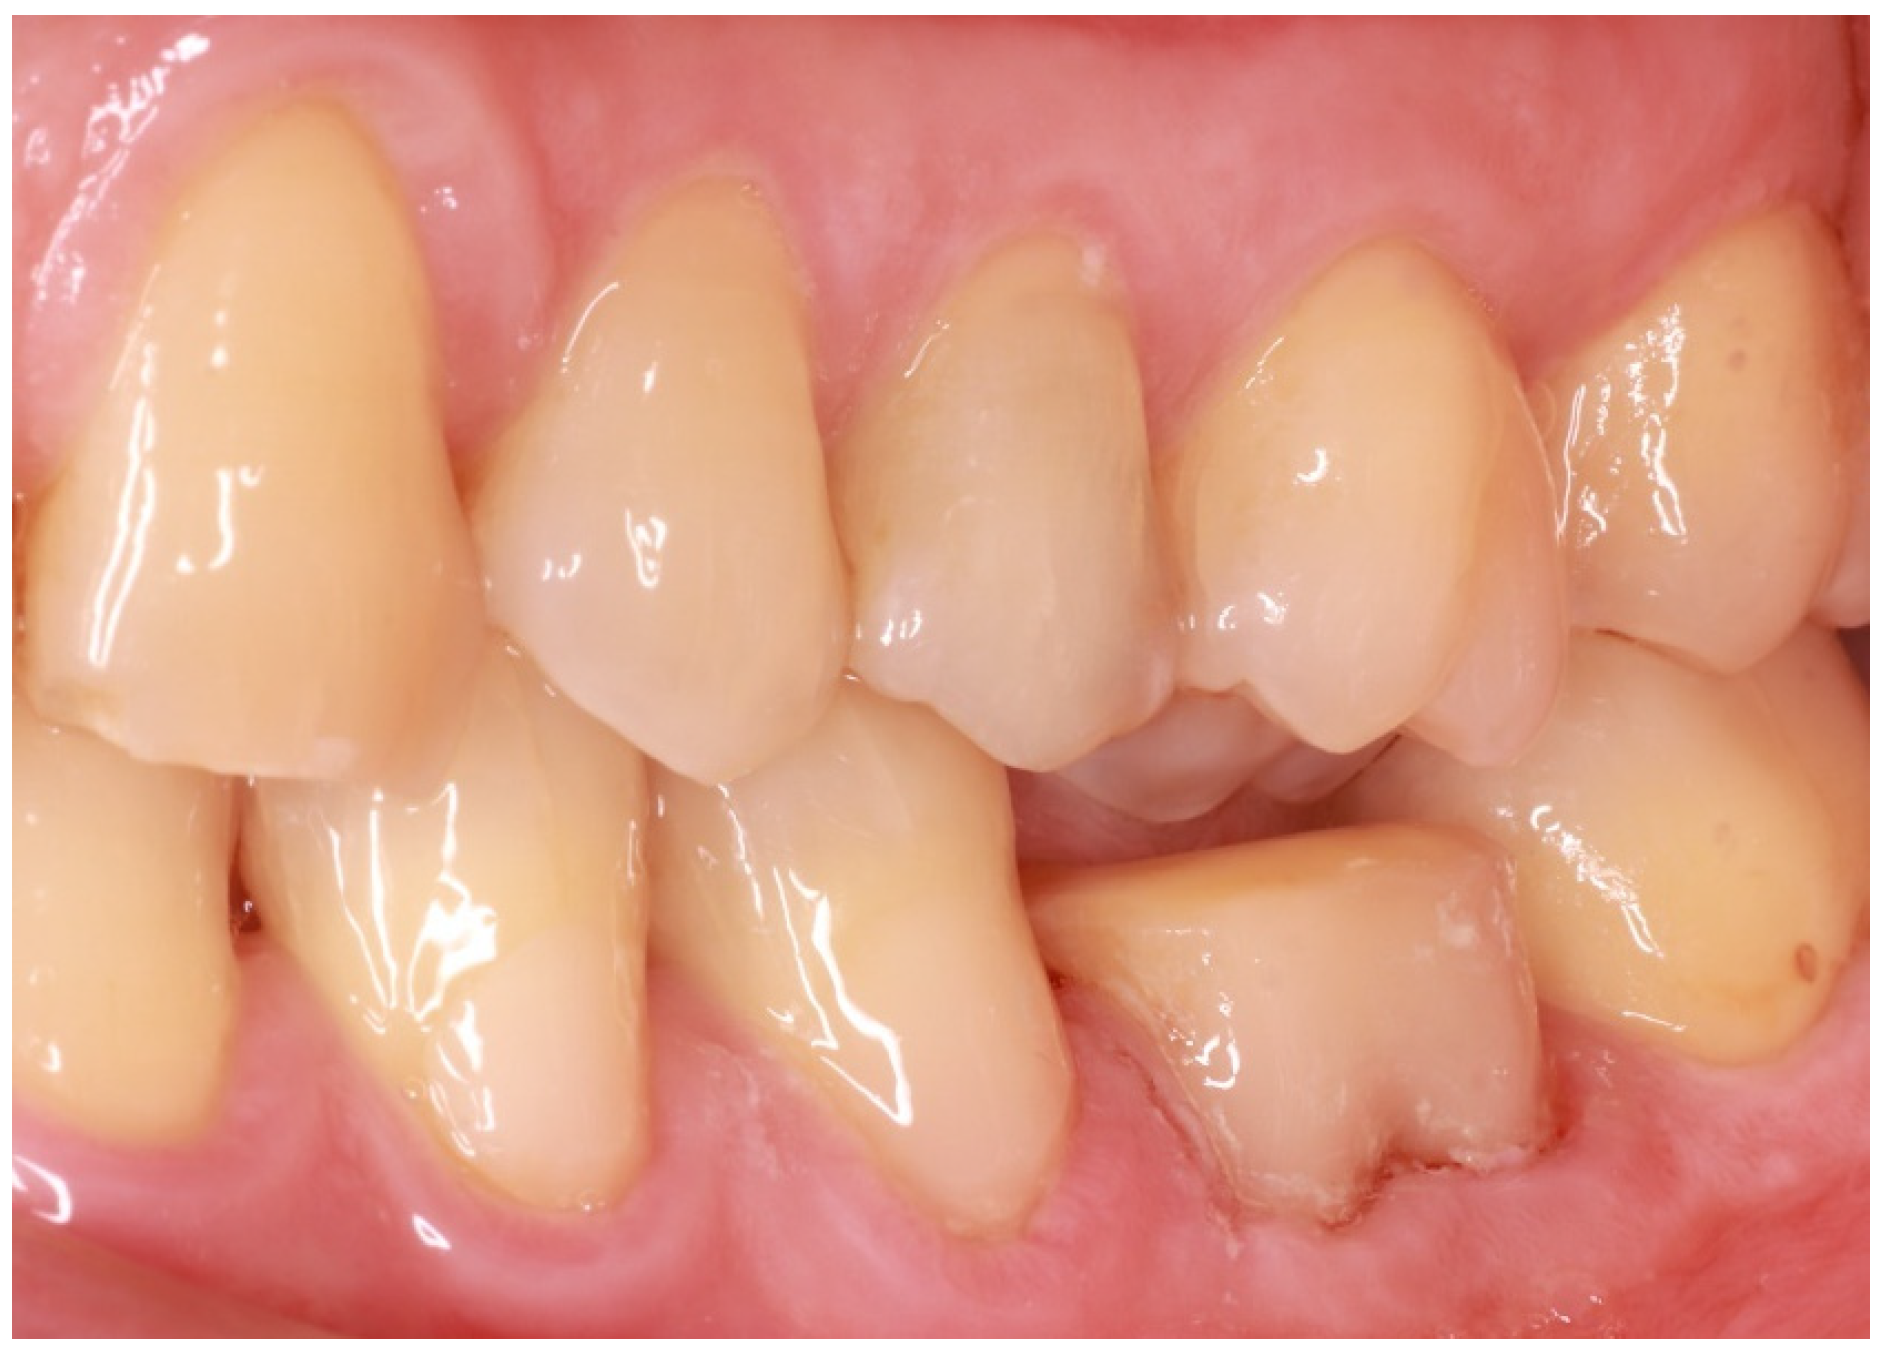

As endocrowns primarily gain retention from adhesive cementation procedures, steps in order to increase micromechanical retention should be incorporated in the applied protocols [11]. In the case described and after the successful endodontic reintervention, the technique of immediate dentin sealing (IDS) was applied on the freshly cut dentin after rubber dam placement [12]. Dentin bonding agent and flowable composite were applied on exposed dentin after removal of the superficial 2 mm of gutta-percha in order to acquire adequate composite resin thickness to avoid microleakage. Cuspal reduction was also performed at this stage so as to both acquire enough interocclusal space for the restorative material of choice, which, in this case, was lithium disilicate, and confirm the presence of dental walls of adequate thickness (Figure 3). Lithium disilicate was chosen because of the positive results regarding the survival rates reported by clinical trials [13].

Figure 3. Confirmation of adequate interocclusal space presence.